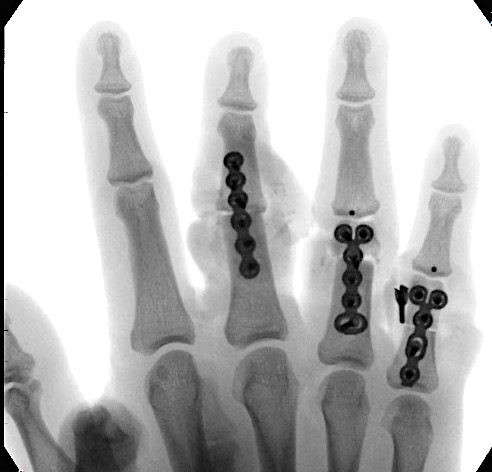

Case 2:

A 20-year-old male suffered a complex multi-digit injury of the right hand requiring revascularization and stabilization of both proximal phalanx and PIP joint fractures (Figs 5 - 8). Multiple plates, including the rotation correction plate from the 1.5 module of the VA Locking Hand System were used for fixation. The Variable Angle Locking system is ideal when only two screws, either proximal or distal, are able to be inserted due to space limitation.

One major advantage of variable angle technology in very distal phalangeal fractures is the ability to be extremely flexible with a wide range of fixation options. Freedom of implant placement assists early mobilization, vital in these complex fractures with associated soft-tissue trauma.